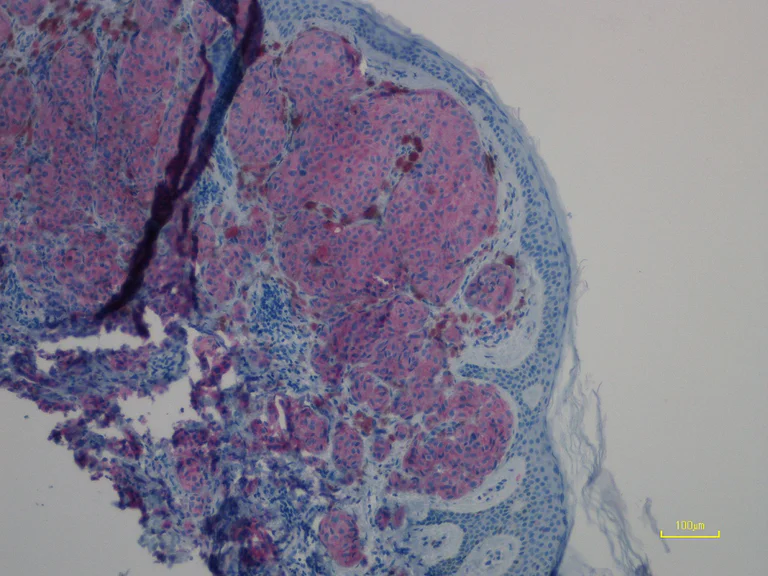

Immunohistochemical analysis of paraffin-embedded human primary malignant melanoma tissue (mutation status : NRAS Q61R) labeling NRAS with ab227658 at 1/100 dilution for 30 min at RT. The tissue was counterstained with Hematoxylin. Heat mediated antigen retrieval was achieved by using EDTA buffer pH 9.0 before IHC staining.

This image is courtesy of an anonymous collaborator.